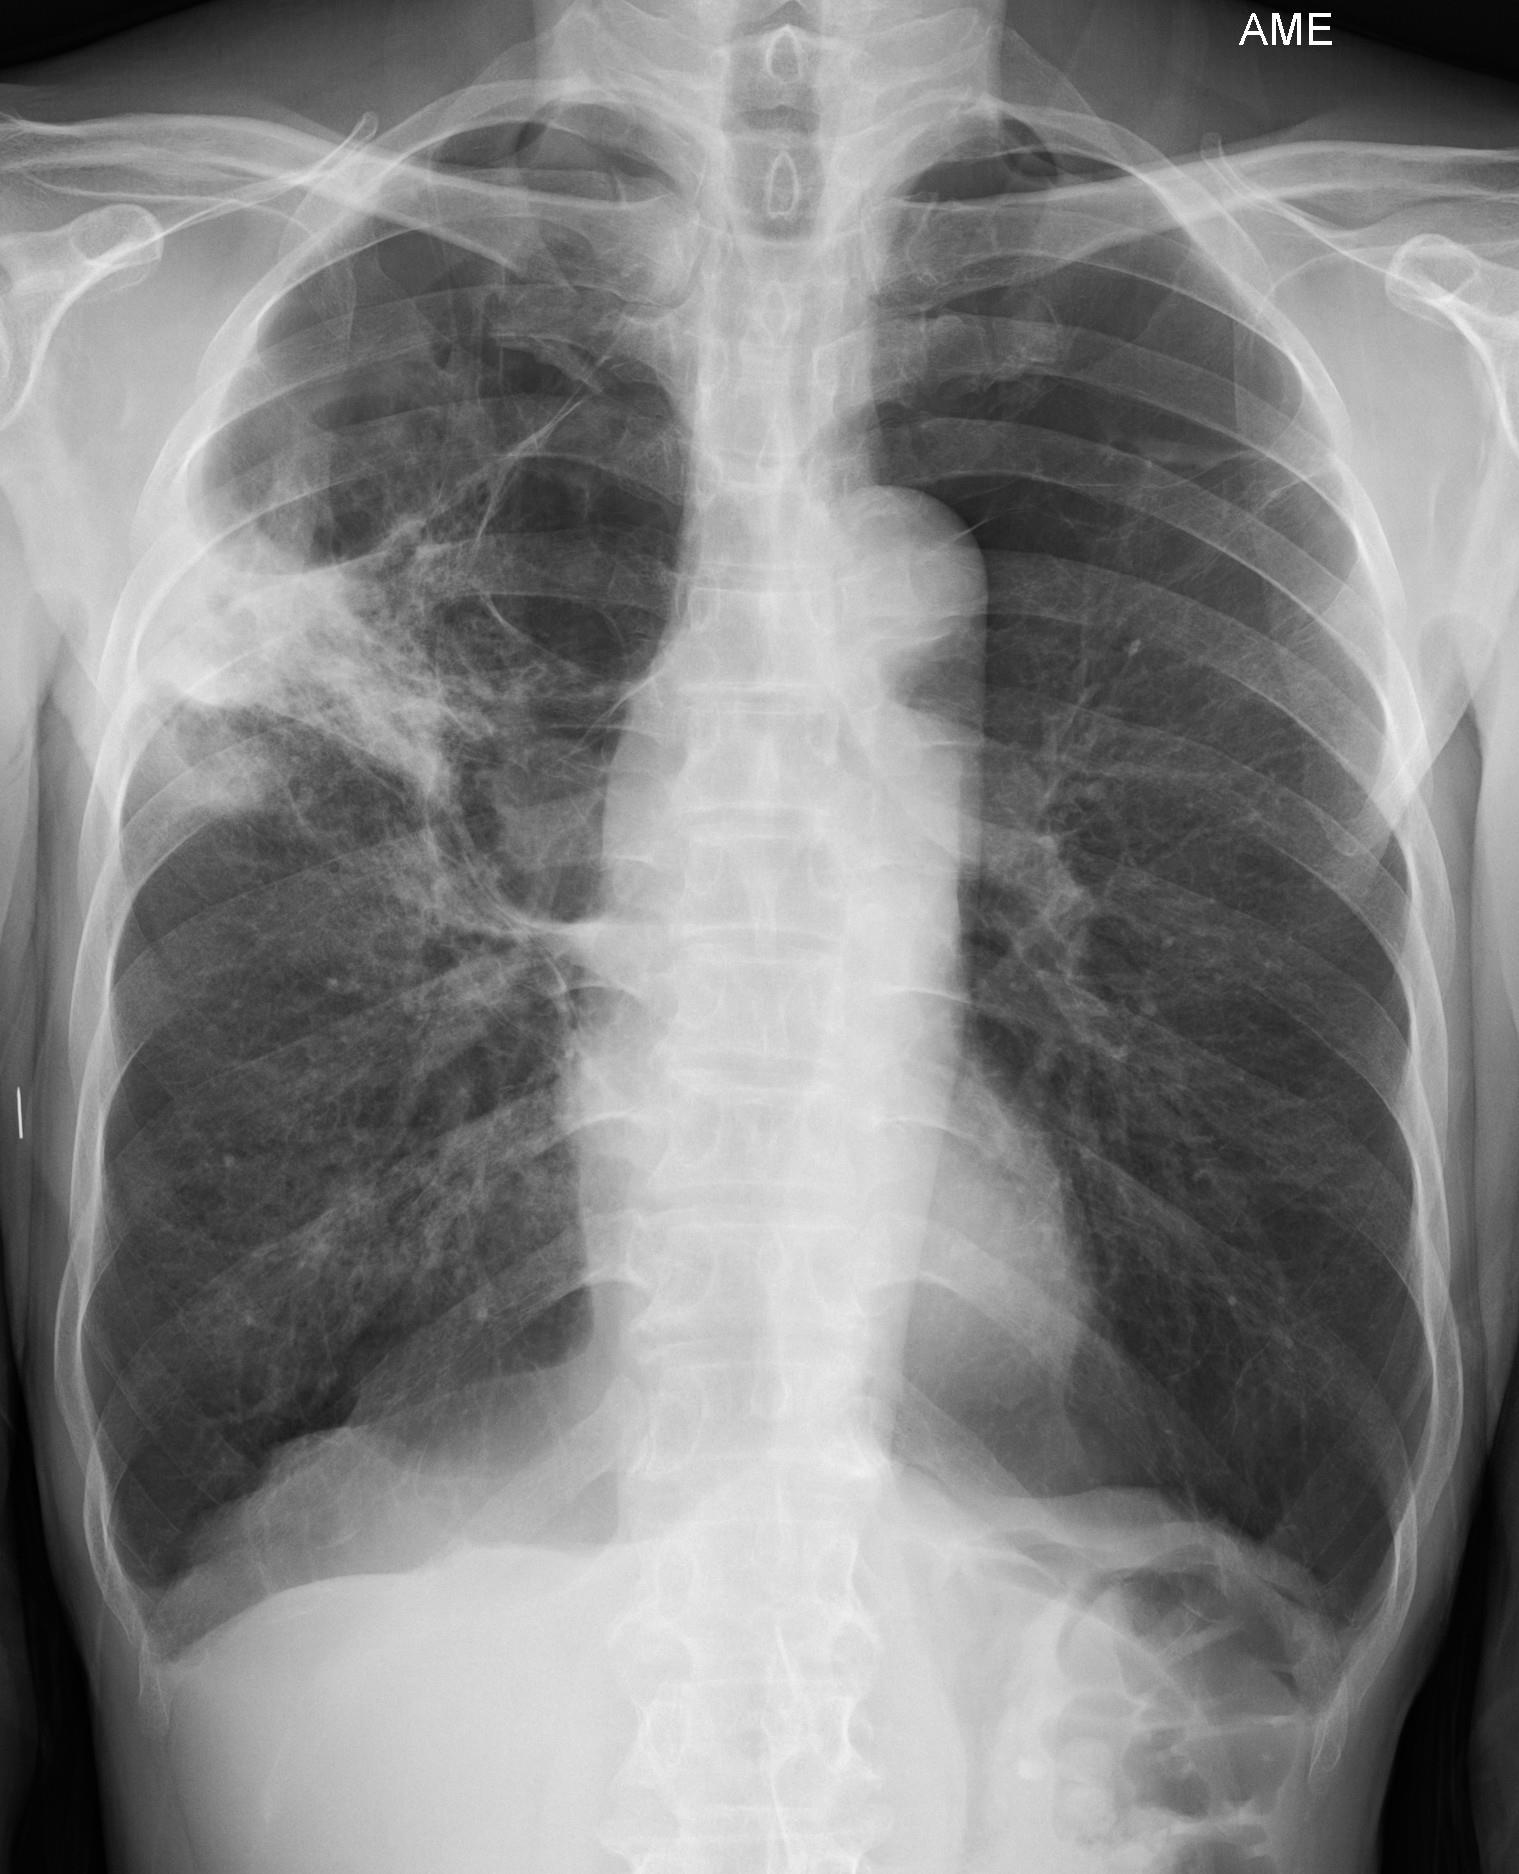

37a - Pretreatment:right upper lung consolidation in a background of bullous emphysema.

37b - Post 9 months of TB treatment.